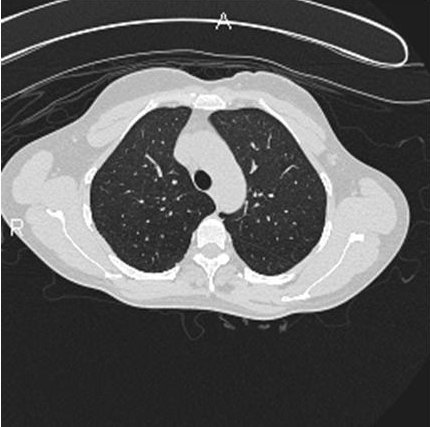

The patient in question was completely removed from further hot tub exposure and additionally received a short tapering course of oral corticosteroids. She showed complete resolution of the radiographic and pulmonary function abnormalities, and is currently symptom-free. Her follow-up computerized tomography of the chest is shown in Figure 3.

Figure 3: Computerized tomography of the chest two months after cessation of exposure and steroid therapy